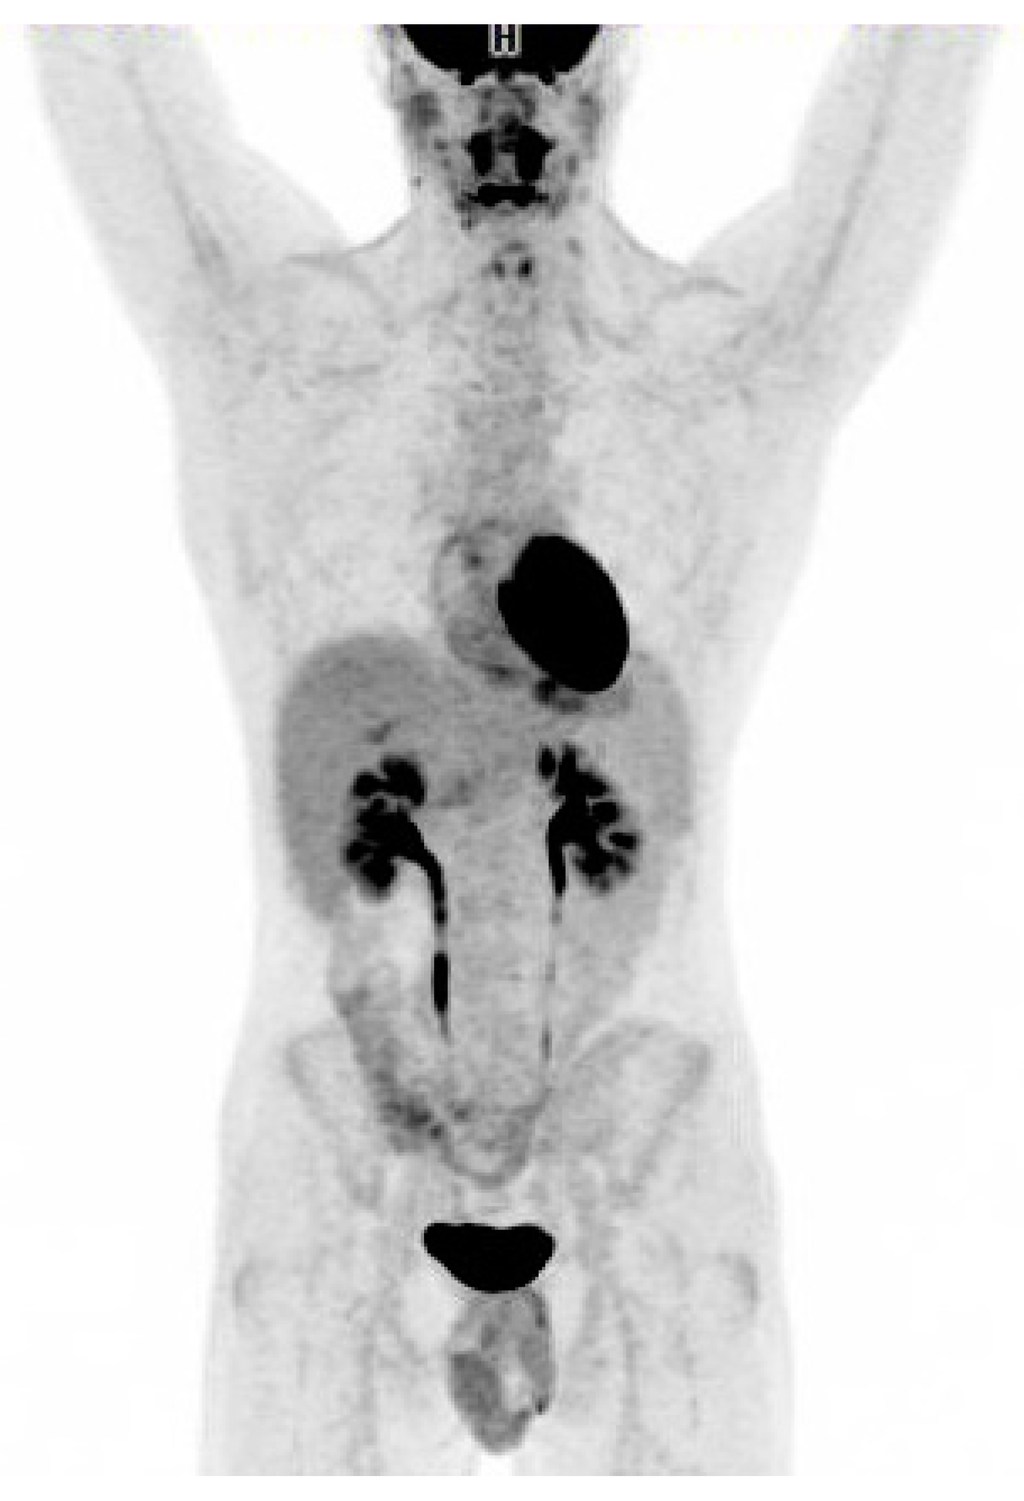

Figure 2. Additional diagnostic workup drawn a day prior to the 18F-FDG PET/CT became available showing positive EBV VCA-IgM and negative EBV VCA-IgG indicating acute infectious mononucleosis. CMV-IgM was furthermore positive. HIV and hepatitis panels were negative. Given the patient’s age, the clinical course with no past medical history and acute EBV titers, the patient’s abnormal 18F-FDG PET/CT scan was most likely secondary to acute EBV infection and no lymph node biopsy was performed. The patient was closely monitored. After a week he had resolution of symptoms clinically, ALT had increased to 461 U/L, LDH to 780 U/L. Twenty days after the initial 18F-FDG PET/CT scan the patient was feeling well, he had regained his appetite and returned to daily activities although still complained of tiredness. ALT = 193 U/L, LDH = 295 U/L. At this time both EBV VCA-IgG and EBV VCA-IgM antibodies were positive. CMV IgG was negative and CMV-IgM was borderline indicating a previous false positive CMV-IgM probably induced by the EBV infection. Follow-up 18F-FDG PET/CT scan in the patient performed 7 weeks after the initial scan (Figure 2) revealed complete metabolic response. Except for one lymph node which had decreased in size from 2.0 cm to 1.2 cm, all the other lymph nodes had regressed to normal size on CT. The size of the spleen had normalized (14 cm). ALT and LDH were normal. Reporting of this case is in accordance with the ethical standards of the institutional and/or national research committee. 18F-FDG uptake in EBV infection has been reported previously in a few cases in children [1] and organ transplant recipients [2]. Only two cases of 18F-FDG uptake in acute adult EBV infection have previously been reported [3,4]. In conclusion, this case illustrates acute adult EBV infection in a non-immunocompromised adult with EBV-induced lymphadenopathy that mimicked malignant lymphoma on 18F-FDG PET/CT scan. It highlights inflammation as one of the most well established causes of falsely interpreting 18F-FDG PET/CT as suspicious of malignancy. Any inflammatory process can demonstrate hypermetabolic activity because of the high degree of glucose metabolism by activated cells of inflammation [5,6]. As always, the benefits of 18F-FDG PET/CT in diagnostic work-up should be viewed in light of the radiation burden to the patient.